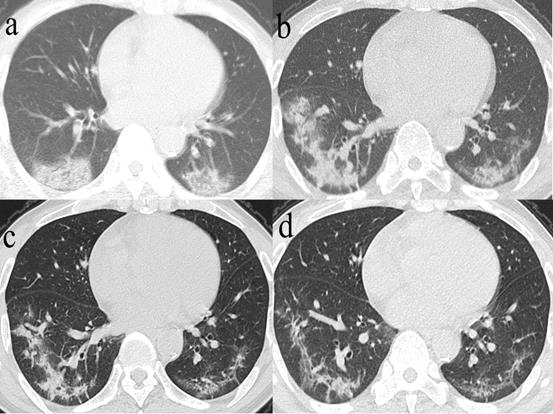

Figure 4

Series CT scans in a 61-year-old man with COVID-19 pneumonia. a. Scan obtained on illness days 2 showed GGO that affected the right middle lobe and left lower lobe. b, Scan obtained on illness days 9 showed an increased extent of GGO with little parenchymal bands. c. Scan obtained on illness days 19 showed absorption of abnormalities, with GGO and little parenchymal bands. d. Scan obtained on illness days 33 showed obvious absorption of abnormalities. Only GGO could be observed. The patient was discharged on illness days 36.